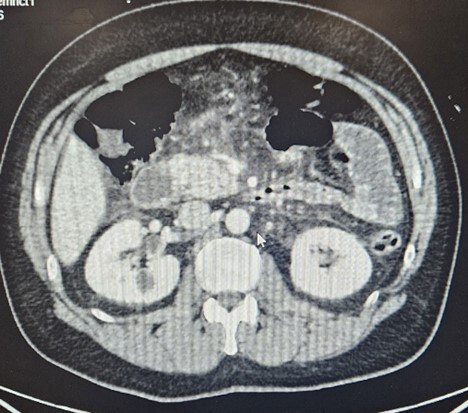

A contrast-enhanced CT scan of the abdomen and pelvis demonstrated acute interstitial edematous pancreatitis without biliary dilatation, necrosis, or peripancreatic fluid collections (Figure 1).